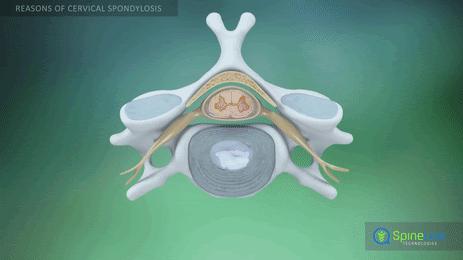

大家可能对颈椎间盘突出也算是耳熟能详了,我们给大家简单的复习一下为什么颈椎间盘会突出。在我们颈椎这两个椎体之间有着重要的结构,那就是颈椎间盘,它是由包绕在髓核外面的纤维环,髓核以及椎体两侧的纤维软骨终板构成的。当人们的颈椎使用时间比较长,使用的比较过度以及自然的老化等原因,椎间盘就可能向周围突出,髓核可能会变得越来越干燥,不再像以前充满水分,充满着弹性,两块椎体之间的高度也会明显的变小。而我们的身体为了维持这个高度,增加颈椎的稳定性,慢慢的就会有骨赘形成。而无论是突出的椎间盘或者是增生的骨赘,都有可能刺激到神经,出现各种各样的症状。大家需要有一个明确的概念,那就是颈椎间盘突出不一定会有症状,很有可能是一种影像学上的表现,但是当突出的椎间盘压迫到了神经,出现了疼痛等症状,我们才称之为颈椎间盘突出症。